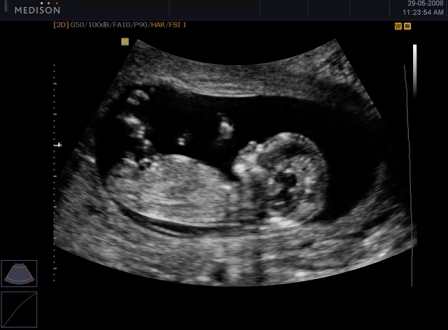

Девочки, назрел такой вопросик тем, кто делал УЗИ на 12 неделе : вам говорили пол ребёнка? Ошибались ли врачи на этом сроке или всё таки говорили пол ребёнка правильно?

Вообще врачи говорят что точно пол ребёнка можно определить к 20 неделях, так как на этом сроке уже все органы малыша развиты, я делала у Соловьева на 12 недели он поставил девочку по вопросом, а на 22 уже сказал что точно девочка